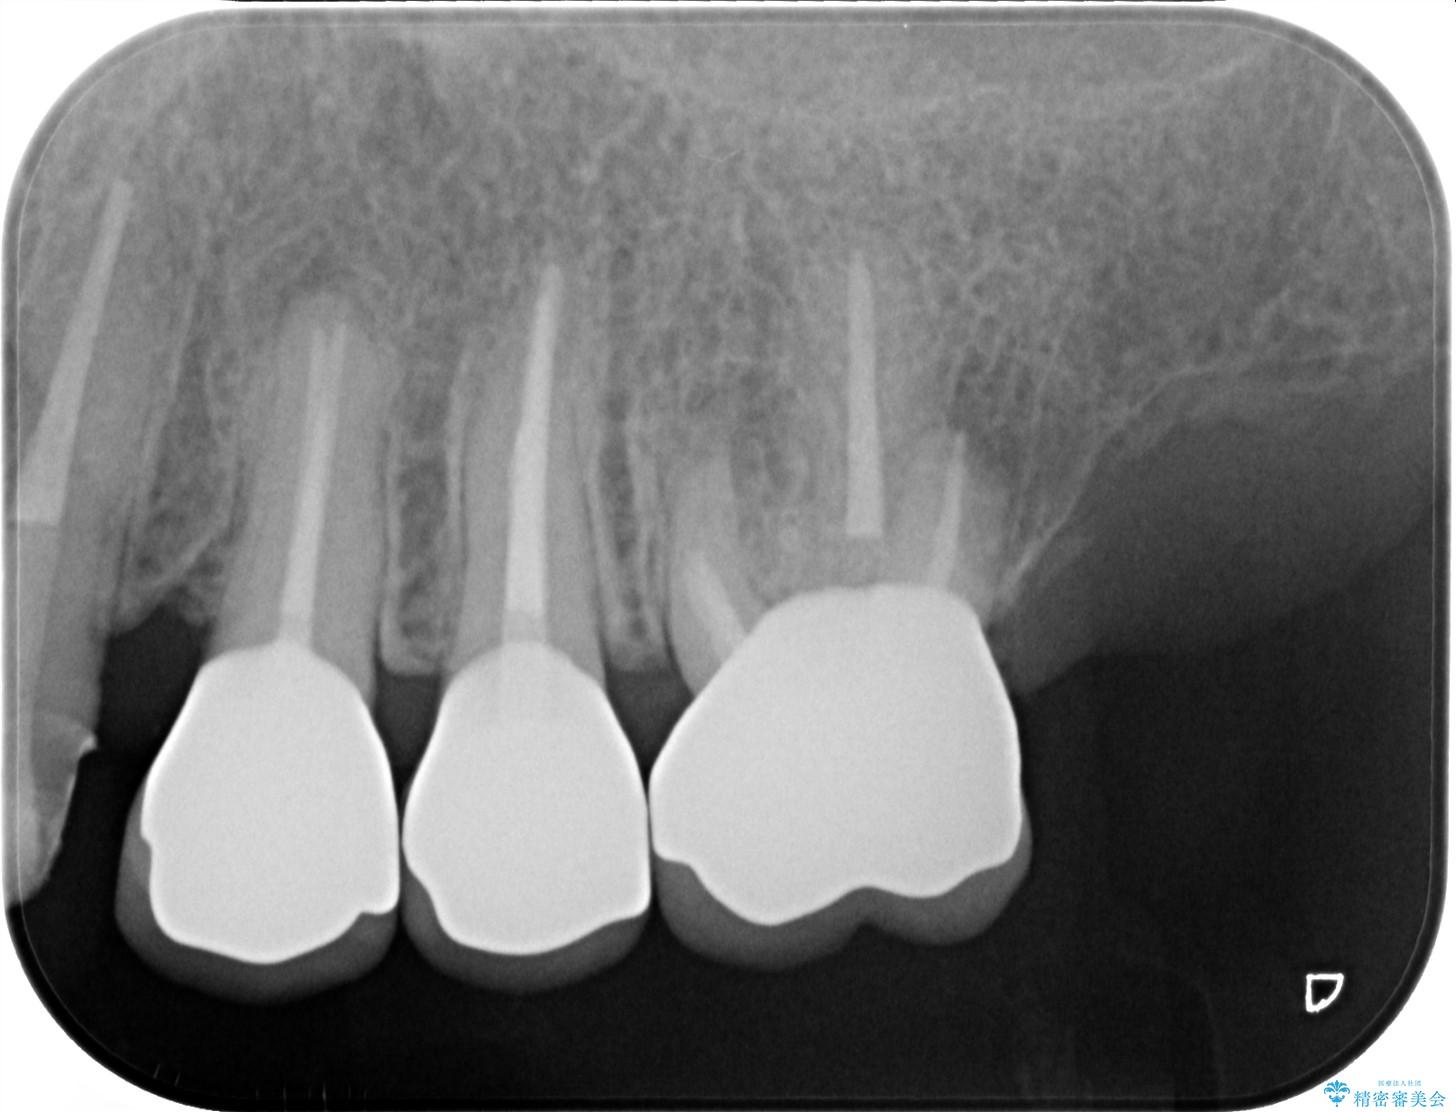

クラウンが装着されておらず、つぎはぎだらけの処置歯を、精度の高いセラミッククラウンを用いて歯ブラシのしやすい環境整備を行っていきます。

セラミッククラウンの治療は、天然の歯のような審美性を回復できることも大切ですが、精度が高くきっちりと歯ブラシを行いやすい状態を整えることで虫歯や歯周病の再発リスクを下げることも非常に大切です。